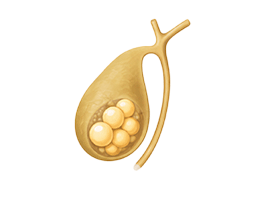

담석증 (Cholelithiasis)